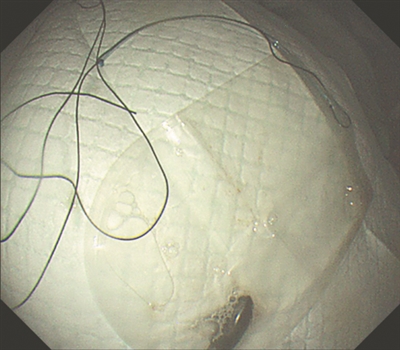

胡健聪尝试用异物钳、圈套器等常规取异物器械,发现都没有办法把磁铁夹住取出。他立即联系手术室,借用手术室腹腔镜常用的无菌标本取出袋,在袋子上绑上丝线,再通过胃镜把标本袋带入胃腔,通过异物钳慢慢像“包饺子”一样把磁铁推入标本袋,最后牵拉丝线经过嘴巴终于把磁铁完整取出。